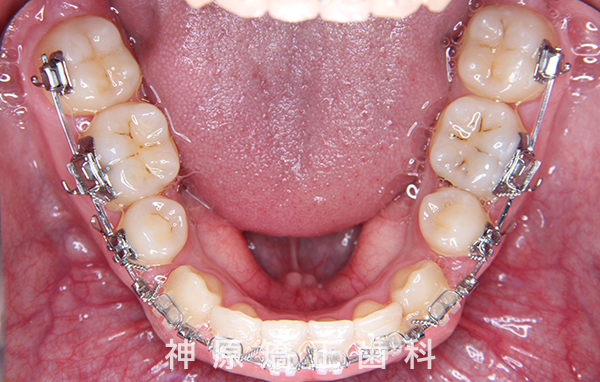

マルチブラケット装着1年後

精密検査の結果、大きな骨格的なずれはありませんでした。しかし、あごと歯の大きさのバランスが悪く、すべての歯を並べると横顔の見た目が悪化する可能性がありました。また、適切な歯軸の獲得も難しい状況でした。そのため、小臼歯を抜歯して適切なスペースを確保し、歯並びを整えることにしました。これにより、ガタガタした歯並びや前歯の噛み合わせの問題が改善されました。